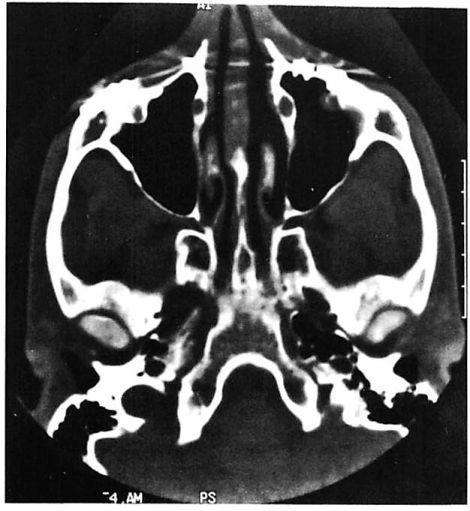

Fig 7. Very high energy Le Fort injury with open crush injury on the left side. Miniplates were used for fixation at maxillary buttresses and zygomaticofrontal sutures. Microplates were used along infraorbital rim and along the zygomatic arch on both sides. Computed tomographic (CT) scan performed 48 hours postoperatively shows loss of infraorbital rim projection on the severely comminuted left side and good projection on less severely injured right side. (A) Preoperative coronal CT shows pronounced lateral displacement of the zygoma on the left side. (B) Preoperative axial CT shows comminution and telescoping of left zygomatic arch. (C) Postoperative CT at 48 hours shows infraorbital rim and malar and arch collapse on left side.

In these injuries we have found that microplates are inadequate to overcome deforming forces from the overlying contused, swollen soft tissue envelope and muscle spasm (Fig 7). Their inability to maintain reduction may be obvious at the time of surgery. Sufficient miniplate fixation is crucial in these injuries. In addition to stabilizing the maxillary buttress at the Le Fort I level,

High-energy zygoma fractures usually occur in combination with Le Fort or panfacial injuries. They exhibit comminution in the lateral orbit as well as lateral displacement and posterior segmentation of the zygomatic arch.